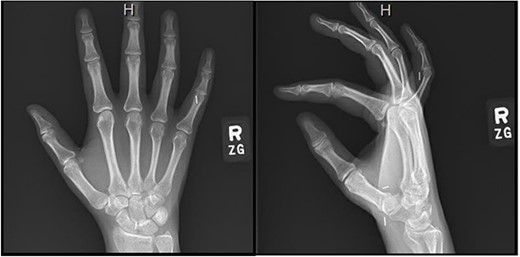

Repeat electromyography (EMG) and monofilament testing demonstrated some continued compression at the carpal tunnel and attempted nonoperative management included night splinting, physical therapy, and a corticosteroid injection (Fig. 1). The patient continued to vocalize complaints of right thumb numbness, sharp pain in her index finger, and an inability to distinguish temperature; therefore, she was subsequently scheduled for a revision CTR.

Semmes Weinstein testing values after redevelopment of right-hand symptoms [17].

Right hand imaging 1-month status post revision CTR demonstrating hemoclip placement with initial asymptomatic migration of a single clip to the small finger proximal interphalangeal joint.